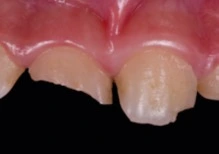

- Trauma gigi: Hiperaktivitas dan impulsivitas meningkatkan risiko jatuh/cedera pada gigi dan jaringan lunak sehingga dapat menyebabkan gigi patah, goyang ataupun terlepas dari soket (gusi).